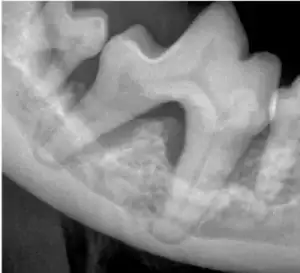

Both the lower right 1st and second molar teeth are affected by severe bone loss due to periodontitis